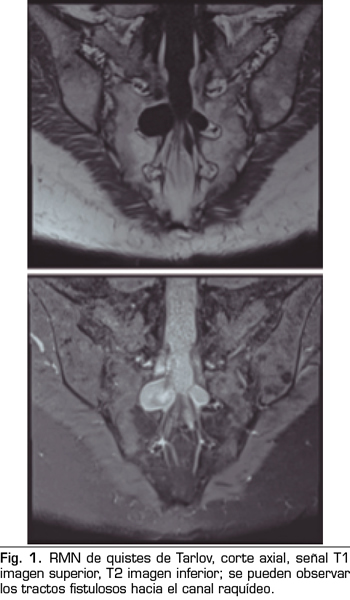

Una de las causas de dolor crónico a tener en cuenta son los “quistes perineurales” o “quistes de Tarlov”. Desde su primera descripción en 1938, son numerosos los artículos en los que se hace referencia. Se trata de lesiones nerviosas que se producen más frecuentemente en la zona sacra (8). En un estudio de Paulsen RD sobre la prevalencia y el drenaje de los quistes de Tarlov, se observó que en 500 pacientes que se sometían a una Resonancia Magnética (RMN) por dolor lumbar, el 5 % presentaba quistes de Tarlov y un 20 % de esos pacientes padecían síntomas relacionados con ellos (9,10). El diagnóstico suele ser casual mediante RMN; la cifra es variable debido a que solo se solicita a aquellos pacientes que presentan dolor lumbar crónico. Dicha técnica es más sensible que la tomografía axial computerizada (11,12).

Se realiza una RMN donde no se observan alteraciones estructurales que justifiquen las dolencias que presenta. Como hallazgo casual se describen quistes de Tarlov a nivel de S2. Se solicita una valoración por el servicio de neurocirugía, quienes dudan que la clínica sea consecuencia de los quistes (Figuras 1 y 2).

No obstante, debemos tener en cuenta las variaciones anatómicas como son los quistes de Tarlov, a expensas de las capas más internas de las meninges, la piamadre y el aracnoides. Estos quistes principalmente se sitúan en la zona sacra y lumbar, y suelen diagnosticarse de manera incidental en el transcurso de una RMN. Aunque la clínica producida por los mismos no es frecuente, se deben tener en cuenta como posible diagnóstico diferencial ante posible dolor lumbar crónico.